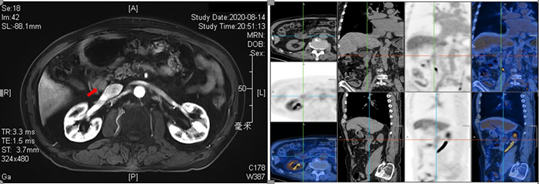

患者男性,74,因“发现CA19-9升高14月,腹痛2月余”就诊。患者14个月前体检发现CA199升高(80U/mL),后至当地医院复查肿瘤指标:CA199 120U/mL。12个月前就诊于外院就诊查CA199 279U/mL、CA242 102U/mL,PET/CT提示左侧肾上腺腺瘤、腹膜后小淋巴结、余未见异常。6个月前至外院复查CA199 1200U/mL。患者2个月前出现腹痛,遂至当地医院消化内科住院治疗,查CA199 158U/mL,腹部增强CT示十二指肠降段内侧壁占位、腹膜后絮片状影与钩突分界不清、腹膜多发肿大淋巴结、胆囊炎。患者半月前就诊于我院门诊,两次行十二指肠镜+EUS检查均未见明显病变,我院PET/CT提示十二指肠降段内侧占位、MT不除外,腹部增强MRI示十二指肠降部良性病变机会大、异位胰腺不除外。患者自诉近期纳差、体重下降约10Kg。我院MDT团队专家就该患者诊断及后续治疗方案展开讨论。

影像科王明亮教授阅患者影像资料后认为:病灶位于十二指肠降部接近球部位置,呈腔外生长、粘膜完好,虽毗邻胰腺,但信号强度与胰腺实质有差别,且中心似有坏死,与异位胰腺不符。该病灶位置偏深,而异位胰腺多位于粘膜下,且十二指肠间质瘤和平滑肌瘤也可以出现该影像学表现,考虑肿瘤性病变可能,异位胰腺不完全除外。

核医学科顾颖涛教授阅患者PET报告后认为:PET/CT图像显示十二指肠降段内侧壁见一大小18.5×15.0mm结节,伴糖代谢轻度增高(最大SUV值约为2.7), 而PET/MRI图像示该病灶T1WI呈低信号、T2WI及DWI呈高信号,最大SUV值为1.4。PET/MRI通常较PET/CT延迟2小时拍摄,该病灶代谢呈下降趋势,考虑为良性病变。